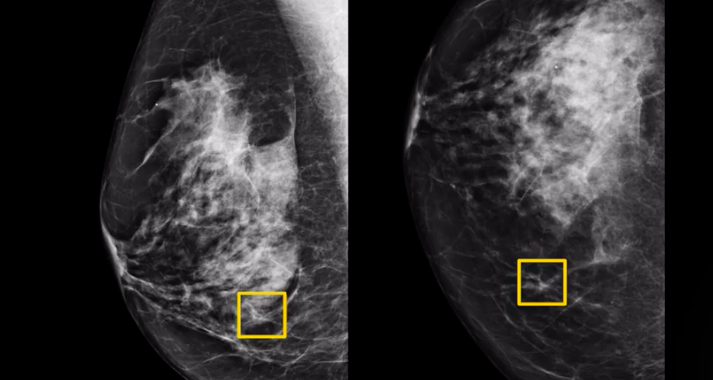

Read article谷歌乳腺癌AI檢測新突破,誤診率遠低于人類醫(yī)生

導(dǎo)語:過去幾年,Google Health部門一直試圖通過人工智能疾病診斷不準(zhǔn)確的問題。 根據(jù)英…